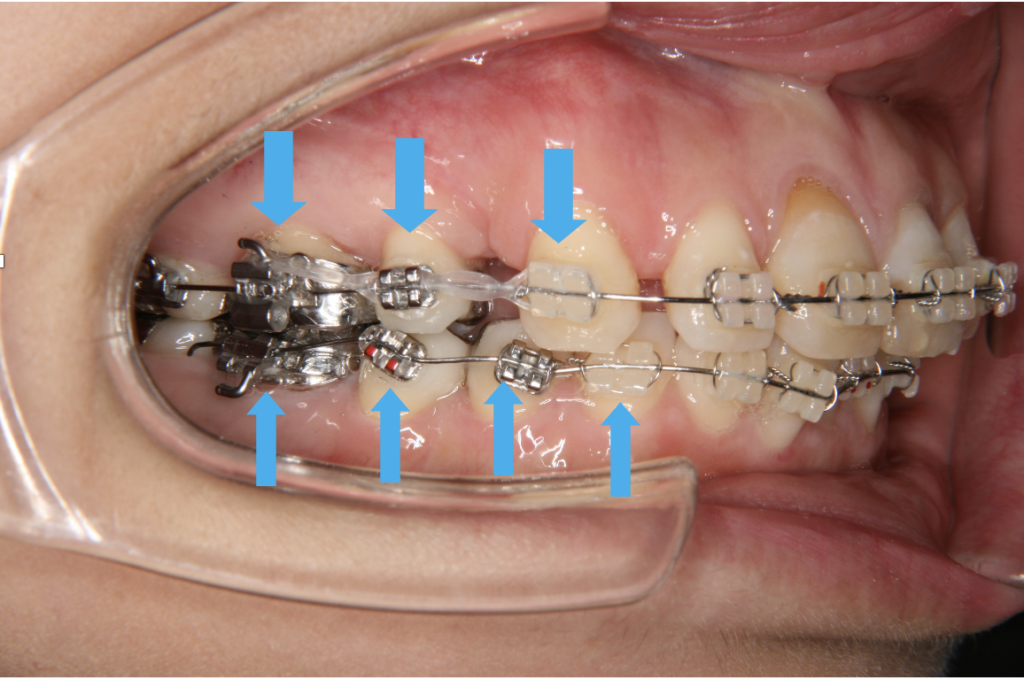

マルチブラケット装置には唇側と舌側がありますが、どちらも食べかすが溜まりやすいのは歯茎と装置の間です。

(図4,5矢印)この部分に付着したプラークはむし歯、歯周病両方の原因になるため優先的にブラッシングによる清掃が必要です。

図4マルチブラケット装置(唇側)